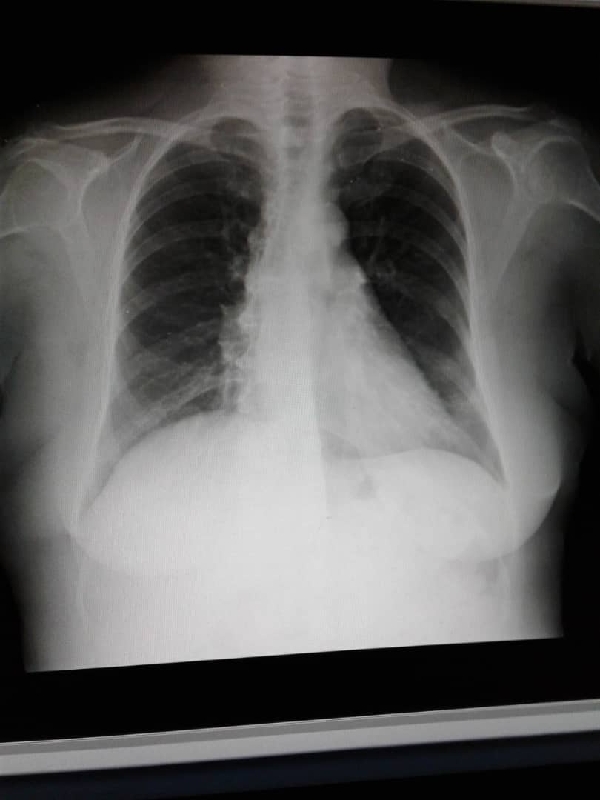

Mi padre Reinaldo Tirado, siempre ha sido asmático, presenta un cuadro de neumonía y la saturación de oxígeno en 84. Razón por la cual necesita ser hospitalizado de emergencia y recibir tratamiento para evitar empeorar.